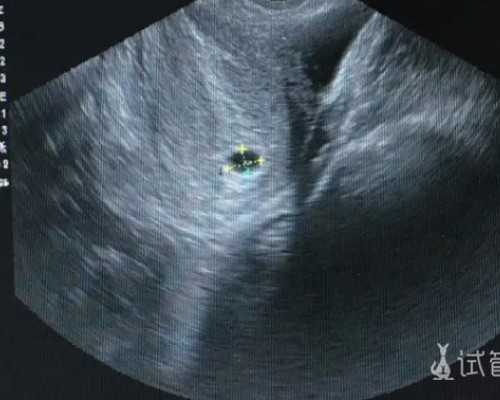

2、B超基础卵泡数(窦卵泡数)基础卵泡数量越多,表示卵巢功能越好。

正常情况下,优质卵泡呈圆形或椭圆形、清亮纯净、边界清晰、壁菲薄、卵泡内无回声区,虽然试管婴儿周期是人为取卵,可若强制取出未成熟的卵子,即便参与受精和妊娠,也易导致受精率及种植率偏低、胎停、流产等。

2。足够数量的卵泡

试管婴儿对卵泡数量当然也有一定要求,有的患者B超监测时卵泡数量较多,可实际的可用卵子却寥寥无几,这是因为B超监测的卵泡包括大大小小成熟与不成熟的卵泡,并不是所有观察到的卵泡都能被最终取出且形成胚胎。